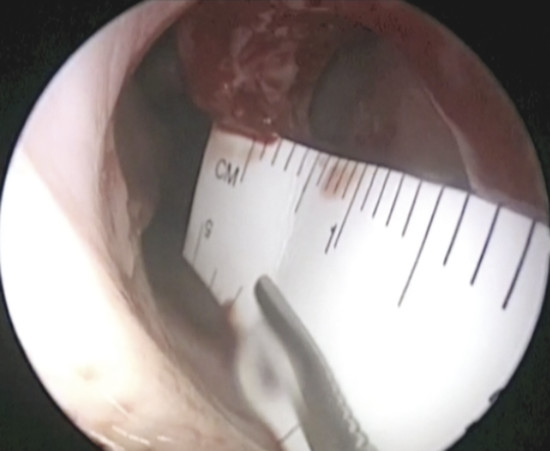

In addition, it is possible to measure the size of the NSP under endoscopic control that is critical when choosing the most suitable surgery (Fig. 6‑4).

The measurement of the defect can be performed in several ways.

The disposable paper ruler found in some surgical pen packs can be trimmed and introduced into the nose to obtain an accurate measurement. If this instrument is not available, the graduated end of the Cottle septum elevator can be carefully inserted and slid against the septum to determine the size of the NSP.

If the defect is not circular, but oval in shape (Fig. 6‑5), it is appropriate to obtain an exact measurement of the major diameters: anteroposterior and craniocaudal, vital in choosing the most appropriate surgical technique. The vertical height of a perforation has been predicted to play a more important role in determining the surgical success than the horizontal length because the main tension between the floor of the nose and the dorsum was critical. 2 The final aspect that must be considered for surgery is the location: anterior, posterior, near the floor, or in the cranial part of the septum. Septal spurs must be identified during endoscopic examination. These should be removed during flap harvesting to get one more large and flexible mucosal layer. (Fig. 6‑6). The septum should be palpated with a sticker or with a cotton tip to discern persistent cartilage between mucosal flaps and determine whether cartilage extends close to the edges of the NSP. 2 In perforations that have occurred after septoplasty, there is usually very little cartilage left, and this makes dissection of the flaps more difficult. In this phase it is also important to check the quality of other intranasal anatomical structures, which represented potential donor sites of grafts or flaps, such as the inferior turbinate, the middle turbinate or the floor of the nasal fossa.